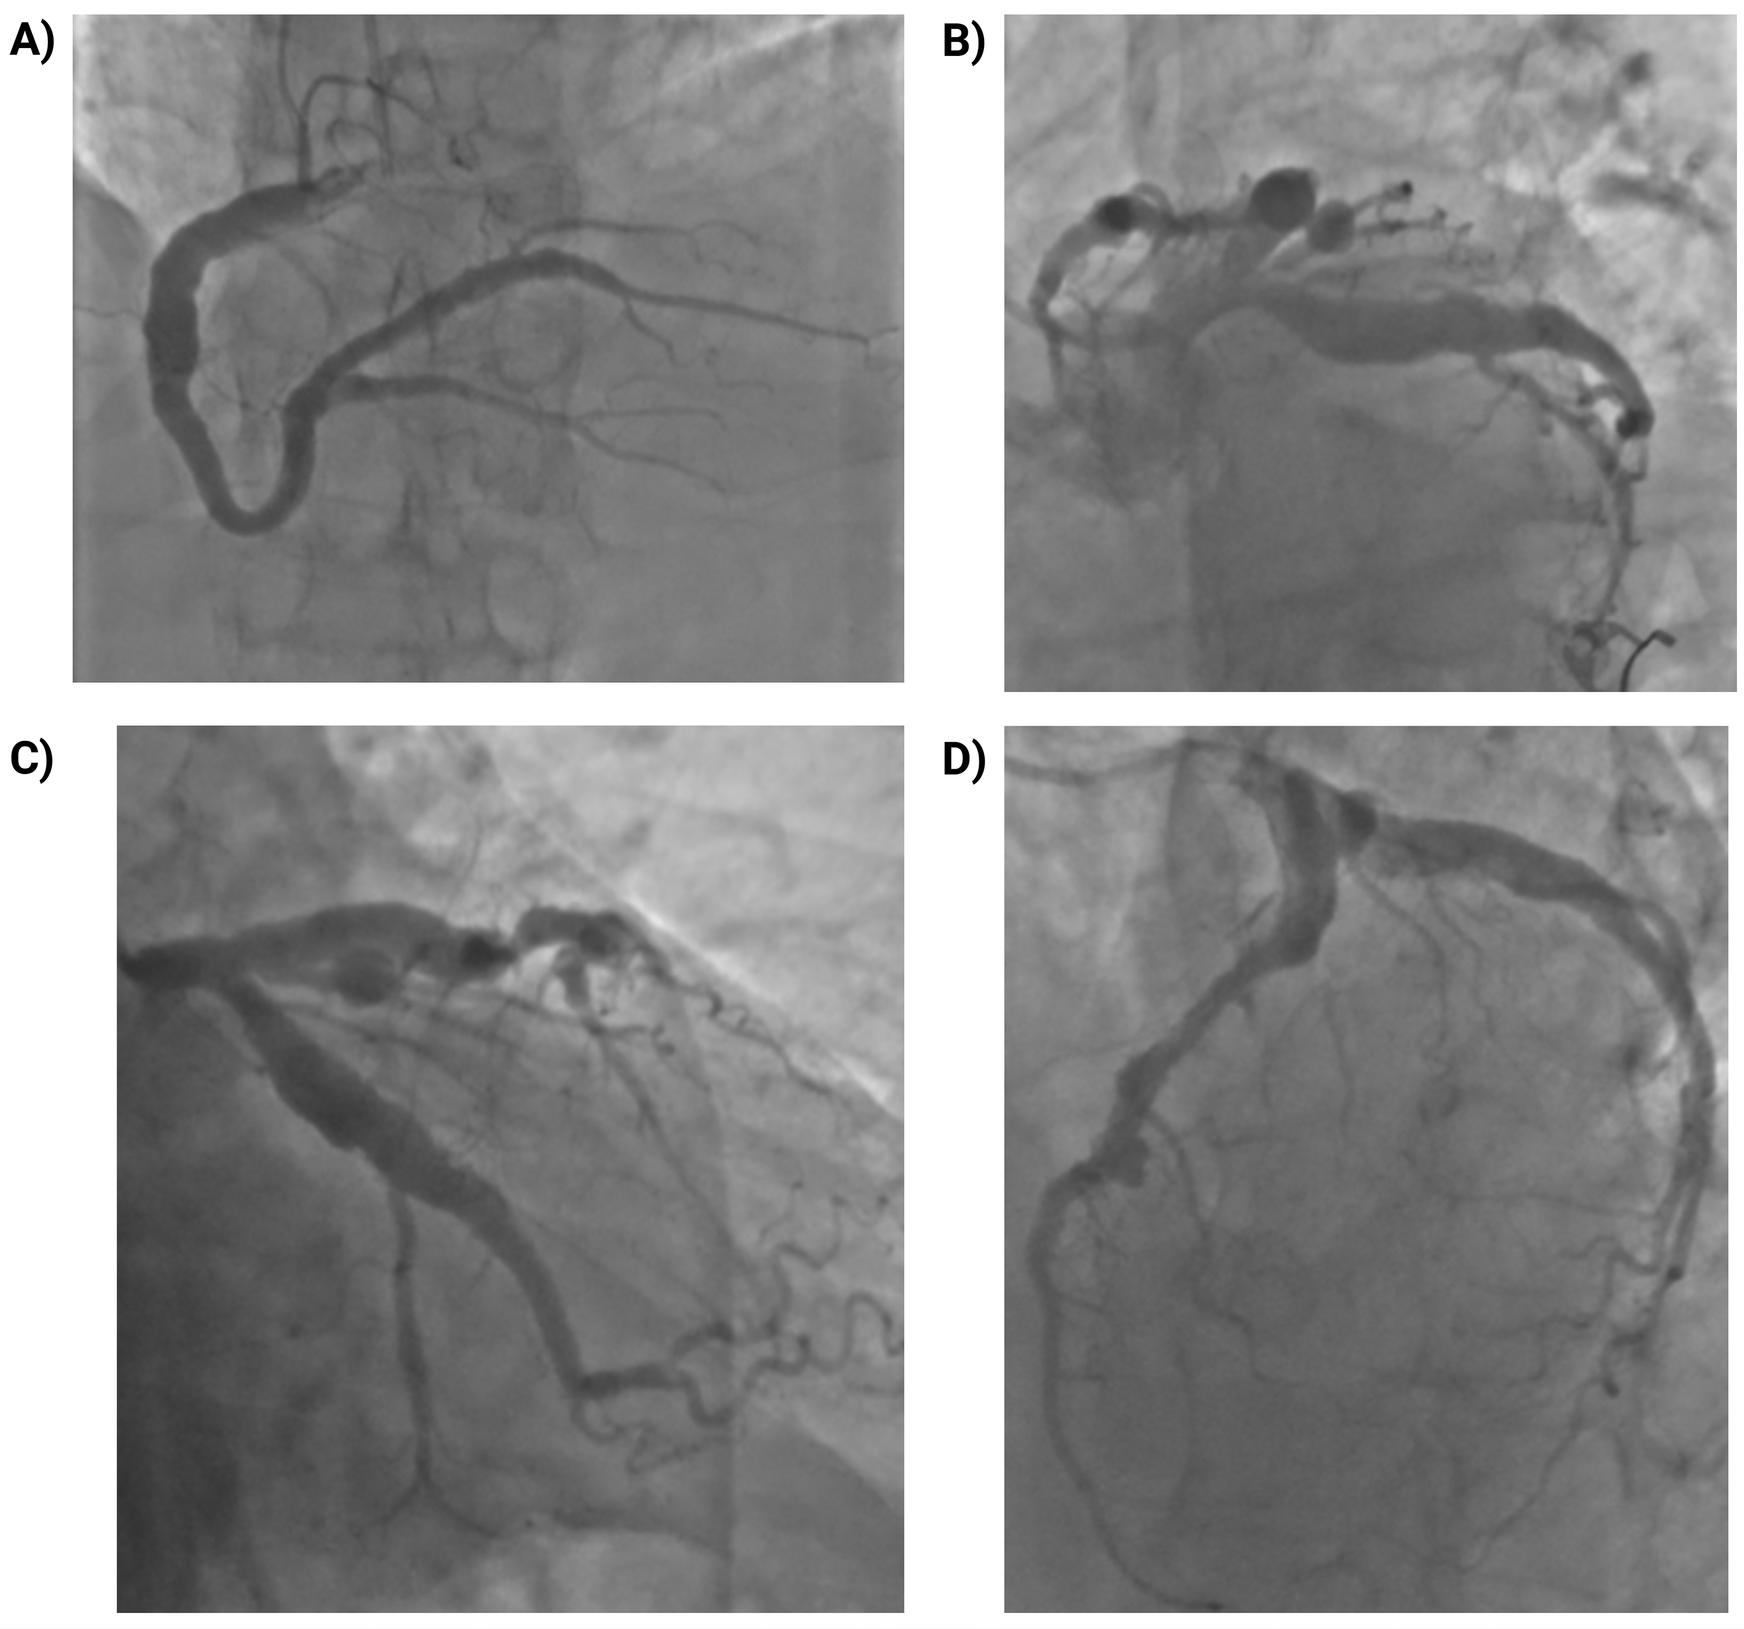

Coronary angiography demonstrated diffuse coronary ectasia involving all major epicardial vessels (Markis type I) with slow TIMI 2 flow. Maximal reference diameters exceeded 8.7 mm in the right coronary artery, 7.2 mm in the circumflex, and 7.1 mm in the left anterior descending (LAD) artery (Figure 1). The mid-LAD showed a prominent myocardial bridge (MB) with a characteristic “milking effect” (∼75% systolic compression), likely accentuated by the surrounding ectatic reference segment (Figure 2). The intermediate branch displayed a severe ostial lesion followed by aneurysmal dilatation (maximum diameter 6.5 mm) and was deemed unsuitable for PCI. Diffuse, non-obstructive atherosclerotic plaques were present throughout the coronary tree without significant fixed stenoseS.

Figure 1

Coronary angiography showing diffuse multivessel coronary ectasia (markis type I). (A) Right coronary artery (RCA): marked ectasia with slow flow (TIMI 2); maximum reference diameter ∼8.7 mm; diffuse non-obstructive atherosclerosis. (B) Left main coronary artery (LMCA): ectatic with markedly enlarged ostium and trunk; no intraluminal lesions. (C) Left anterior descending artery (LAD): marked ectasia with diffuse atheroma; maximum reference diameter ∼7.1 mm. (D) Left circumflex artery (LCx): ectatic, large-caliber vessel with slow flow (TIMI 2); maximum reference diameter ∼7.2 mm; side branches with diffuse non-obstructive plaques.